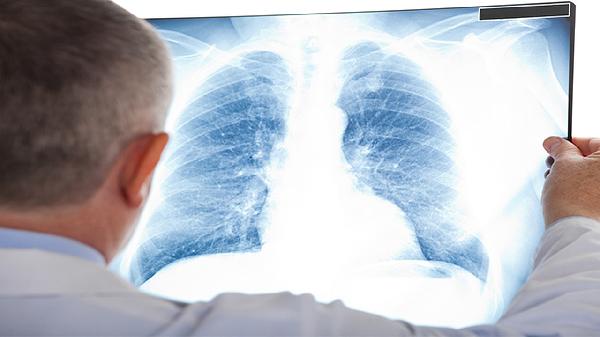

查肺癌通常需要做低剂量螺旋CT、支气管镜检查、病理活检、肿瘤标志物检测、PET-CT等检查项目。肺癌筛查与诊断需结合临床表现和影像学特征,不同检查手段各有侧重。

低剂量螺旋CT是筛查早期肺癌的首选方法,能清晰显示肺部微小结节,辐射量仅为常规CT的1/5。该检查对直径超过5毫米的肺结节检出率较高,适用于长期吸烟者等高危人群的年度筛查。检查前无须特殊准备,扫描时需配合呼吸指令。